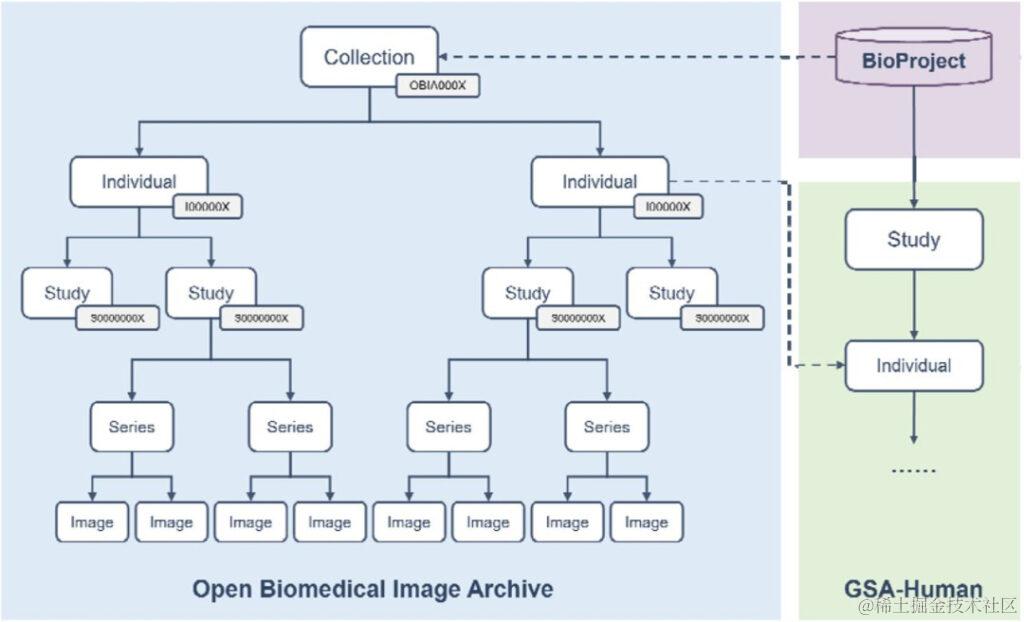

数据库内容及使用——数据模型

如图 3 所示,OBIA 中的成像数据分为 5 种对象类型: Collection, Individual, Study, Series, Image,分别指:

• Collections: 以「OBIA」为前缀,提供完整提交的总体描述;

• Individual: 登记编号以「 I 」为前缀,定义接受或登记接受医疗保健服务的人类或非人类生物体特征;

• Study: 采用以「S」为前缀的登录号,包含对个人进行放射检查的描述性信息;

• Series: 研究可以根据不同的逻辑(如身体部位或方向)分成一个或多个 Series;

• Image: 描述单个 DICOM 文件(Digital Imaging and Communications in Medicine,医学数字成像和通信)的像素数据,Image 与单个 Study 中的单个 Series 相关。

注:DICOM 是一种广泛应用于医学影像领域的国际标准,定义了一套存储、传输、共享和打印医学影像数据的规范和协议,使不同厂商生产的医学设备和软件之间可以相互兼容和交流。

图 3:OBIA 数据模型

基于这些标准化的数据对象,OBIA 将 DICOM 标准定义的图像结构与实际研究项目连接起来, 实现了数据的共享和交换。

此外,OBIA中的每个 Collections 都链接到 BioProject 以提供有关研究项目的描述性元数据;

如若可行,OBIA 的 Individual 可通过 Individual 登录号与 GSA-Human 相关联,后者将成像数据与基因组数据联系起来,供研究人员进行多组学分析。